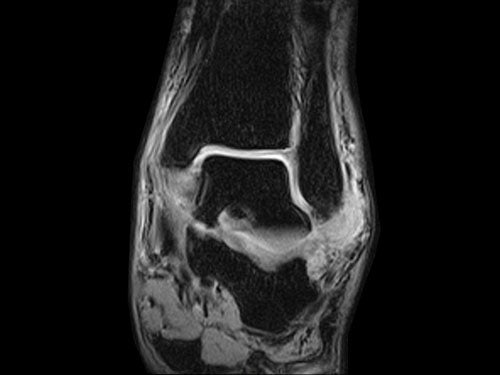

ESAOTE O-SCAN eXP 2016 - Dedicate MRI for Extremities with Cage

ESAOTE O-SCAN eXP  2016 - Dedicate MRI for Extremities

• All Coils (See pictures)